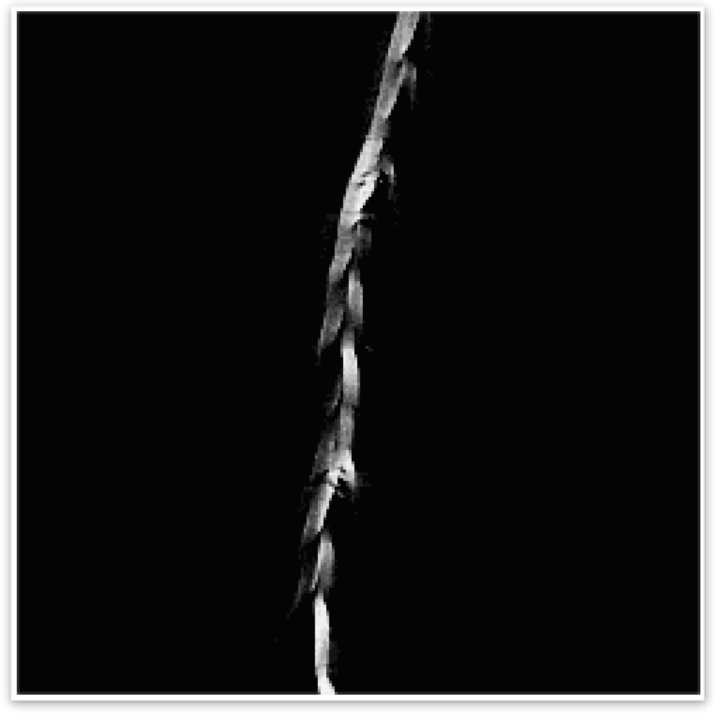

04 运动伪影(Motion Artifact)

若样品在扫描过程中发生轻微移动,例如因振动、热胀冷缩或固定不牢,图像中就可能出现模糊、重影或边界错位。这类伪影常见于扫描时间较长或样品形态不稳定的情况。

运动伪影示意图